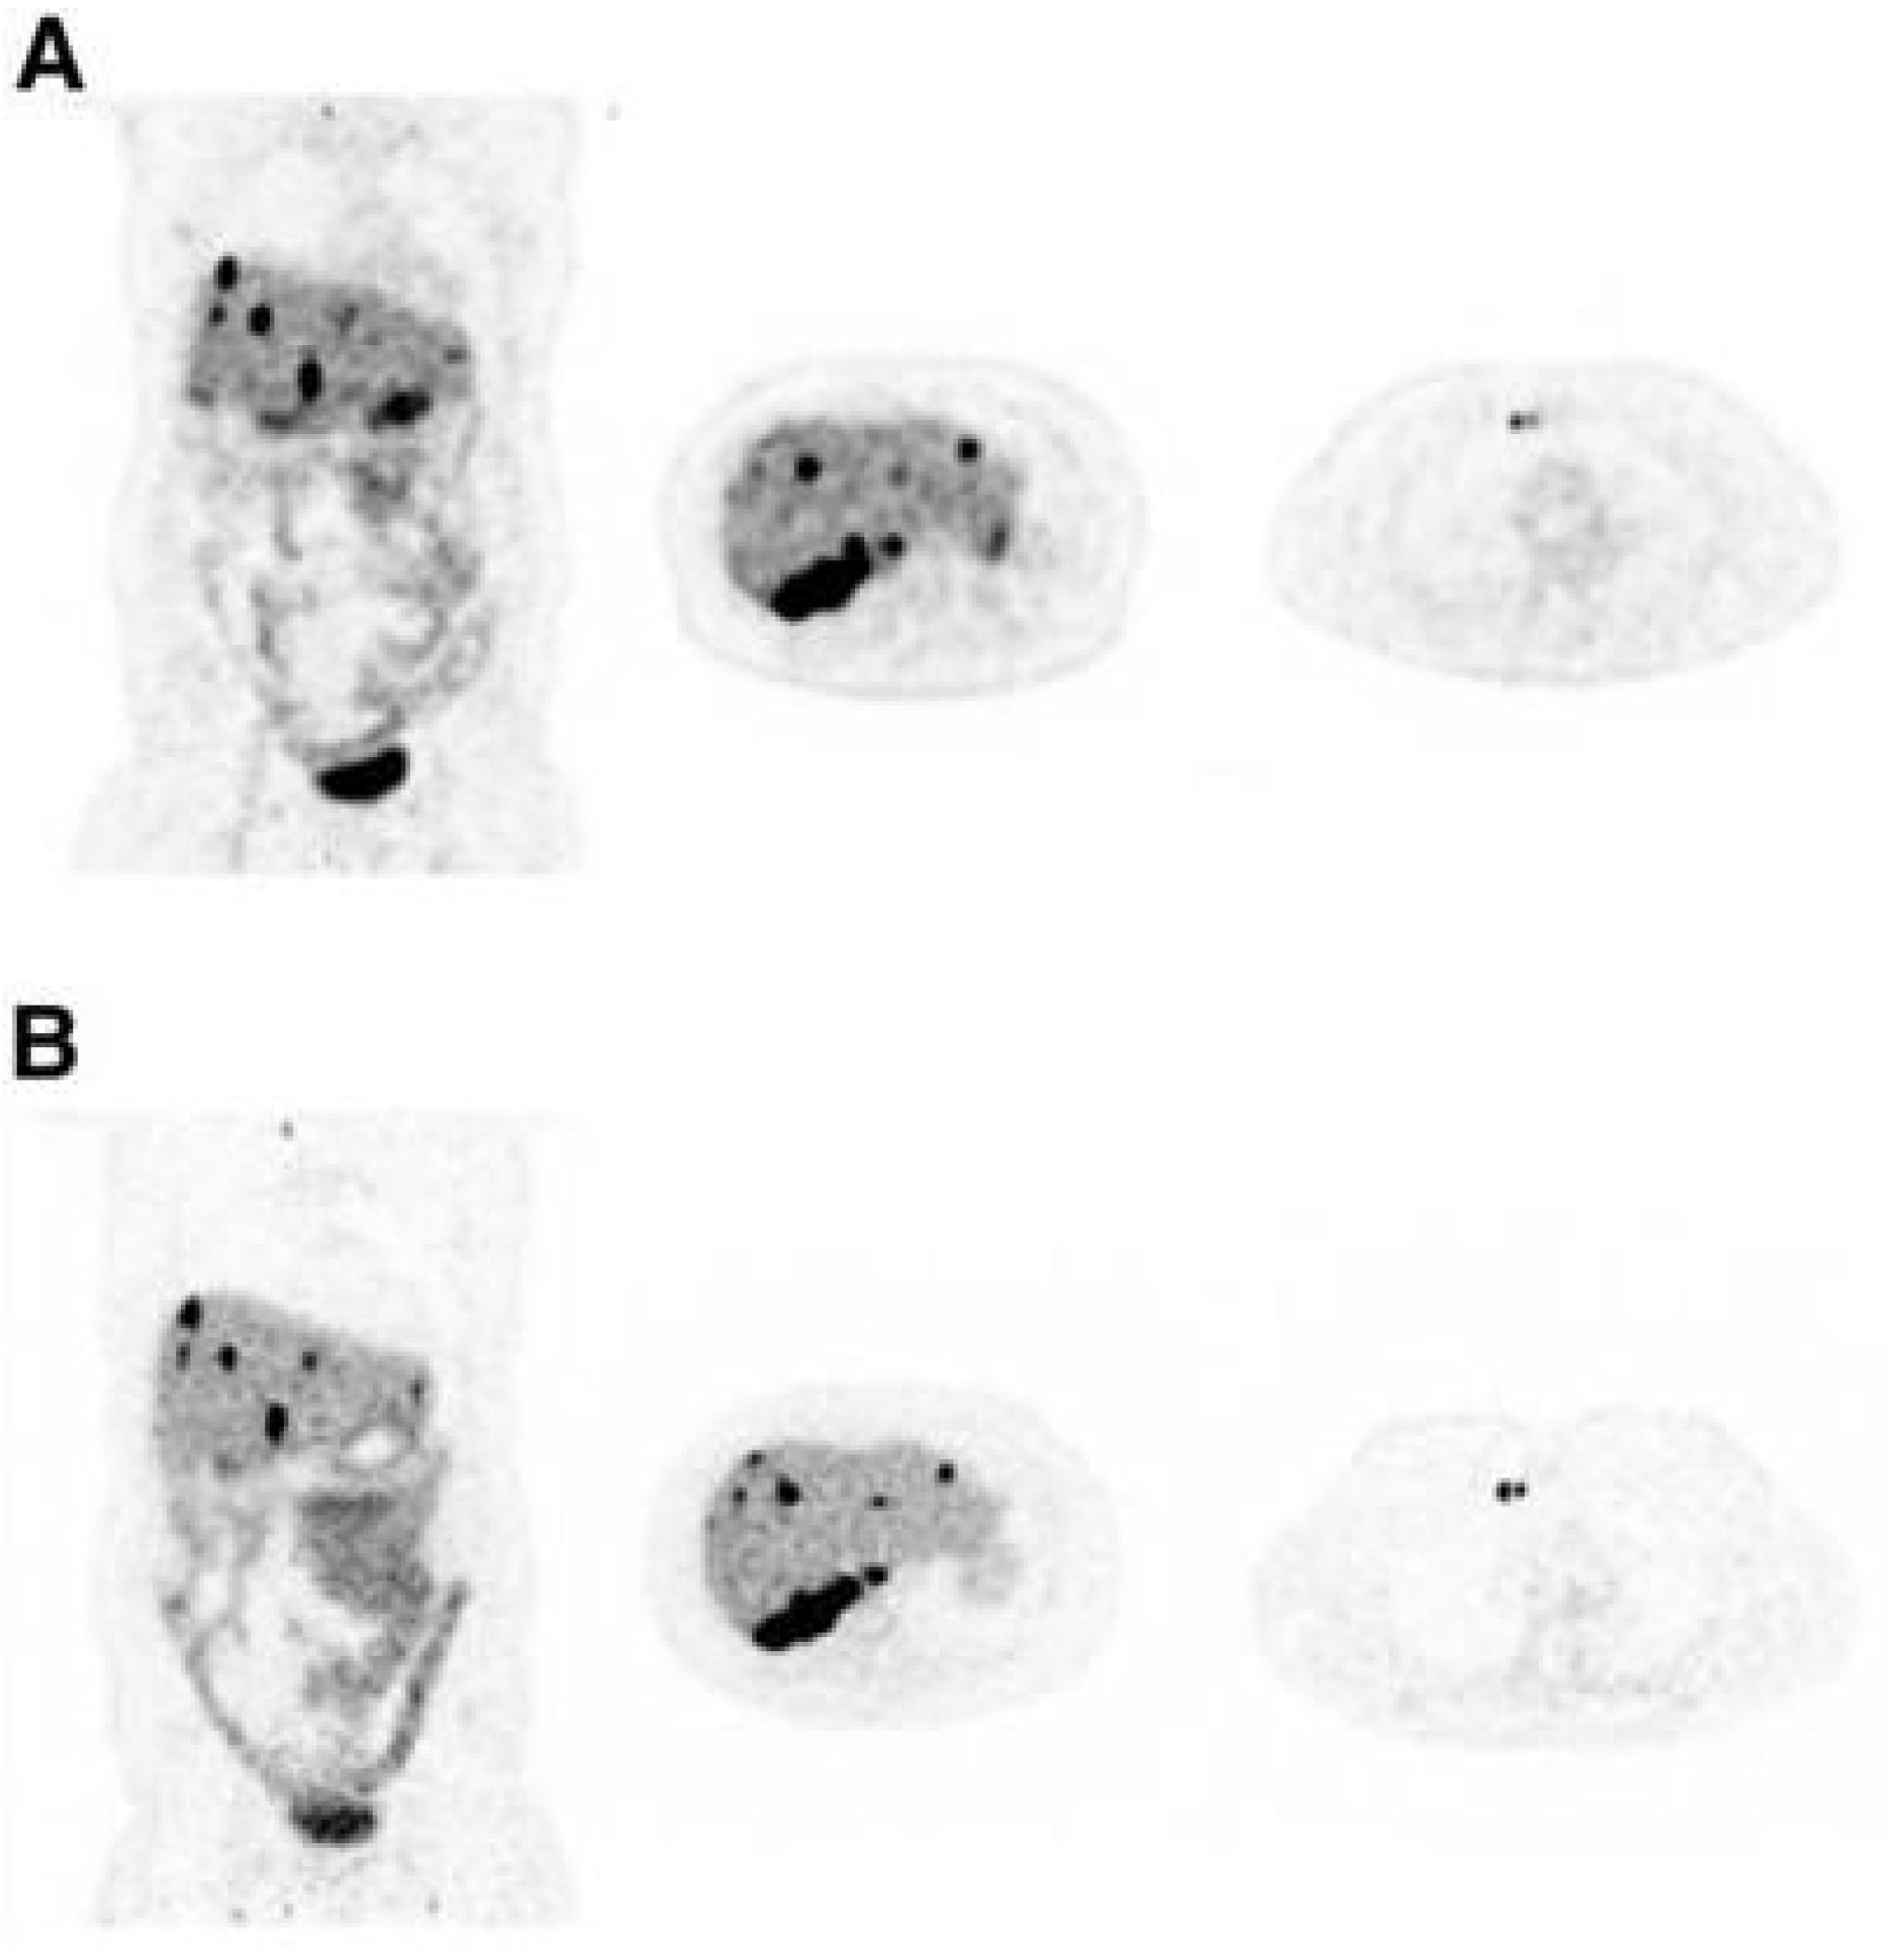

- Van Sluis, J.; Bellido, M.; Glaudemans, A.; Slart, R. Long Axial Field-of-View PET for Ultra-Low-Dose Imaging of Non-Hodgkin Lymphoma during Pregnancy. Diagnostics 2022, 13, 28. [Google Scholar] [CrossRef] [PubMed]